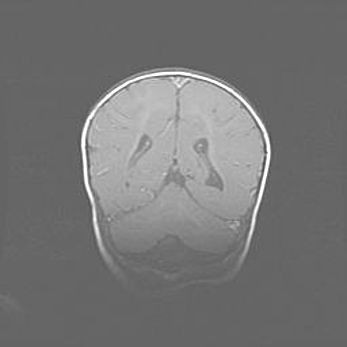

Церебральная ишемия II.

Возраст: 5 дней

Вес: 3400 г

Пол: женский

Окружность головы: 35 см

Срок гестации: 39 недель

Церебральная ишемия – это заболевание, характеризующееся недостаточностью (гипоксией) либо полным прекращением (аноксией) снабжения мозга кислородом по причине закупорки одного или нескольких сосудов. Это приводит к  что метаболическим расстройствам различной степени тяжести в тканях головного мозга, развитию коагуляционных некрозов и гибели нейронов.